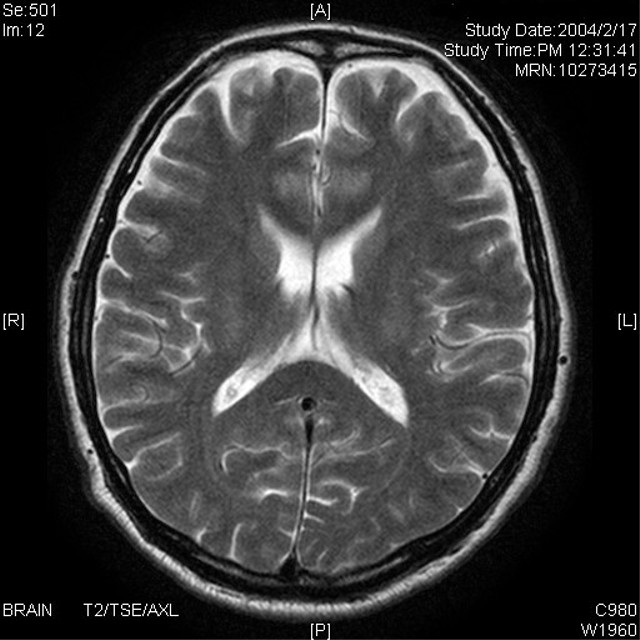

脳梗塞

脳梗塞って以前は高確率で後遺症な病気でしたが

【拡散希望】脳梗塞って以前は高確率で後遺症な病気でしたが、現在は発症後の約4時間以内に「t-PA」という魔法みたいな薬ブチ込めば、後遺症無く普通に治る確率が非常に高いのです。ですので、普段の1.5倍くらいキツイ頭痛で、なんか下半身の脱力感ま...

ガッテンで心筋梗塞の話やってて。血栓が心臓辺りに詰まると心筋梗塞、脳で詰まると脳梗塞なので興味深く見た。凄い痛みでも救急車呼ばない話を聞いて、そうそう私みたいにすぐ救急車呼んだ奴も少しして症状緩和すると、呼ぶ必要無かったかなとか思っちゃうの...

あるイラストレーターさんが脳出血で倒れお亡くなりになった

あるイラストレーターさんが脳出血で倒れお亡くなりになったというのをTLで見かけ、この方の過去の呟き見てみたんだけど、数日前から頭痛を訴えてて恐らく仕事に追われ病院には行けず市販の頭痛薬でしのごうとしてたようだ。数年前脳血栓で倒れた時の自分と...

コロナで脳梗塞を起こしてしまった友人はもう意識が戻る事は無いそうです

コロナで脳梗塞を起こしてしまった友人はもう意識が戻る事は無いそうです。奇跡が起きない限り彼女はあと数日だそうです。まだお子さんは中学生と高校生。心が痛んで仕方がありません。これで知り合いは国内外含めて3人目。悲しさと怒りに毎日襲われます。ど...